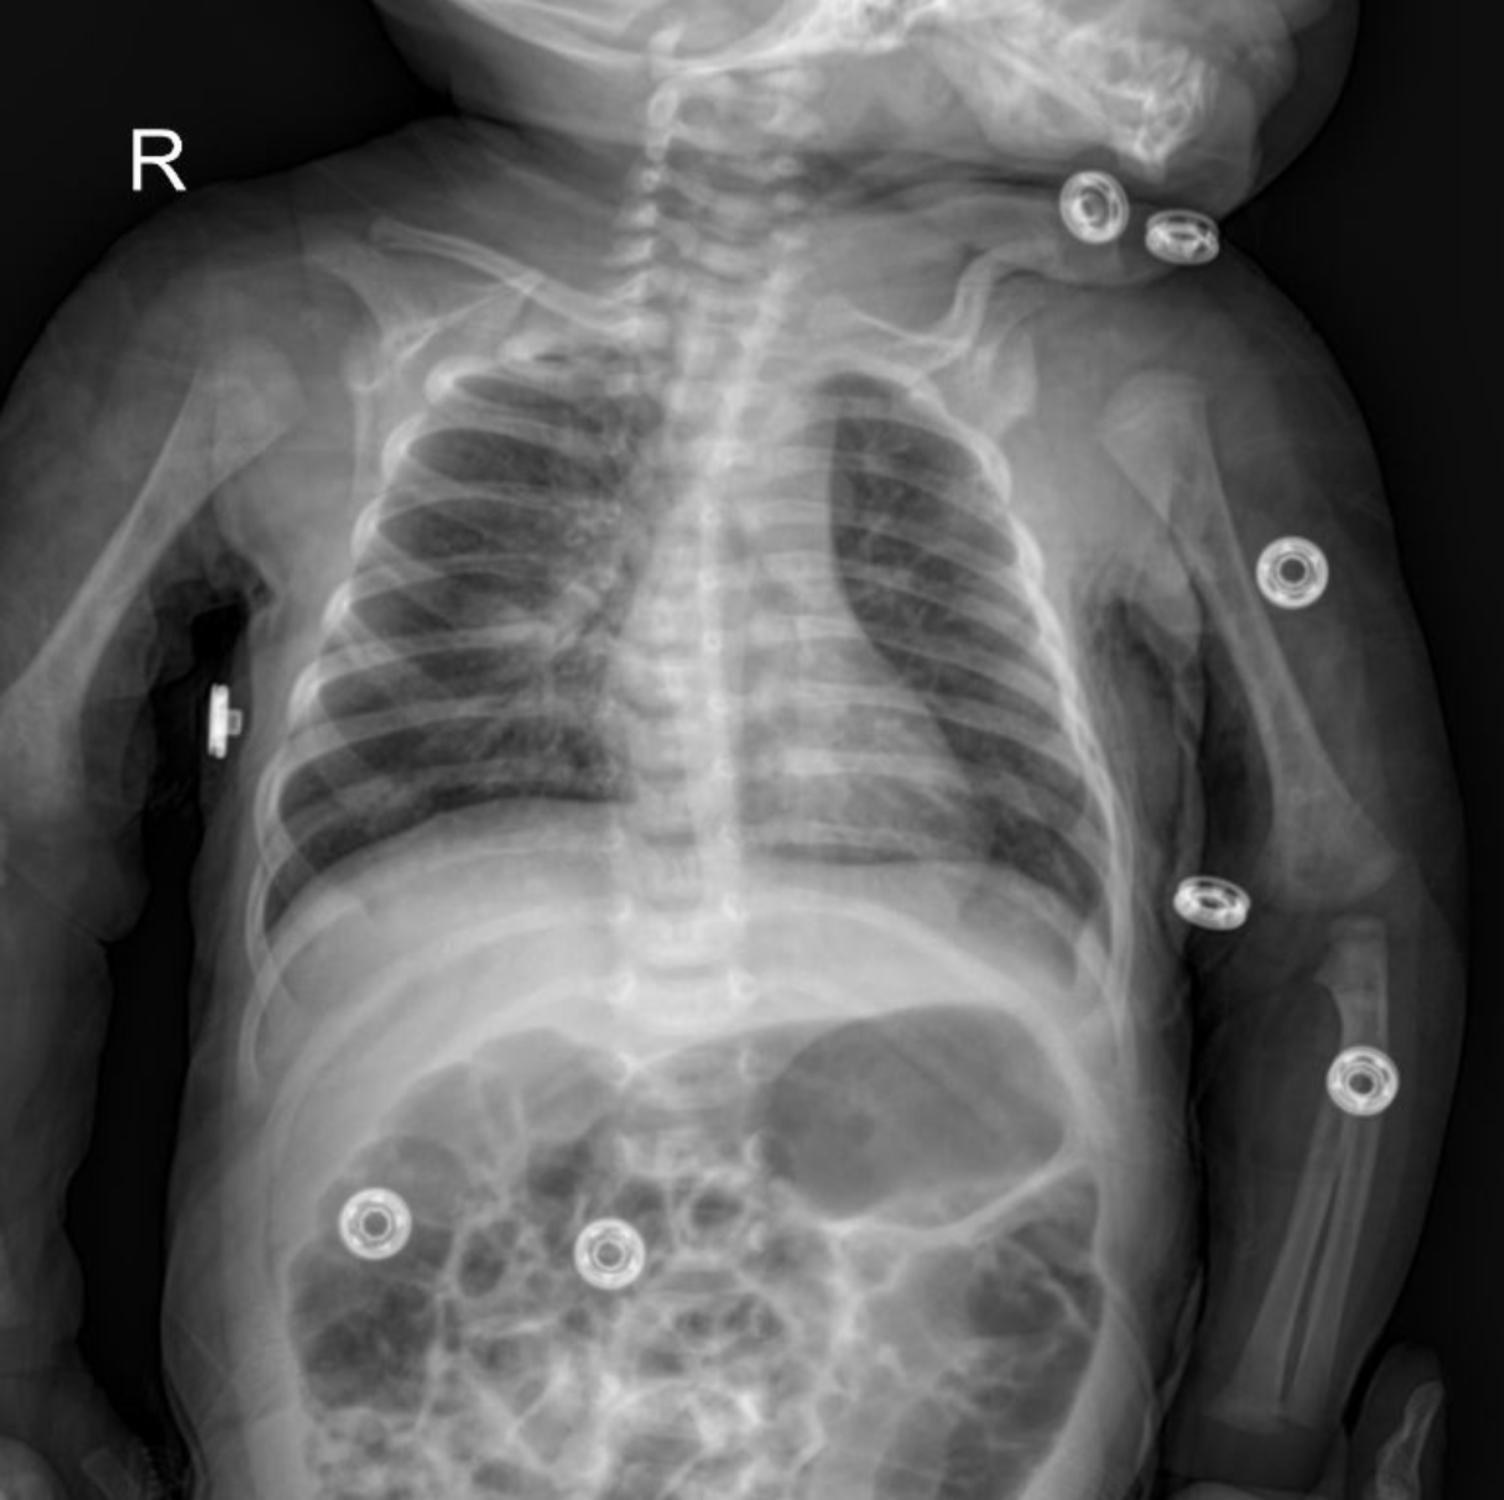

The image shows a frontal chest radiograph of an infant. Key features to observe include:

- Diffuse Bilateral Infiltrates: The most striking feature is the presence of widespread, ill-defined opacities throughout both lung fields. These infiltrates suggest an inflammatory process, consistent with pneumonia.

- Perihilar and Lower Lobe Consolidation: There appears to be denser consolidation, particularly around the hila and in the lower lobes. This indicates areas where the alveoli are filled with exudate, a classic sign of bacterial pneumonia.

- Small Right Pleural Effusion: A subtle blunting of the right costophrenic angle (highlighted by the blue circle) suggests a small pleural effusion, which can accompany pneumonia.

- Air Bronchograms: While not explicitly highlighted, careful inspection might reveal air bronchograms within consolidated areas, further supporting the diagnosis of pneumonia.

- Right-sided Marker “R”: Indicates the right side of the patient.

- Artifacts: The circular metallic objects seen on the patient’s shoulders and limbs are likely ECG leads or other monitoring devices, and should not be confused with pathology.

The combination of diffuse infiltrates, consolidation, and a small pleural effusion on the chest X-ray strongly supports the clinical suspicion of pneumonia in this infant.